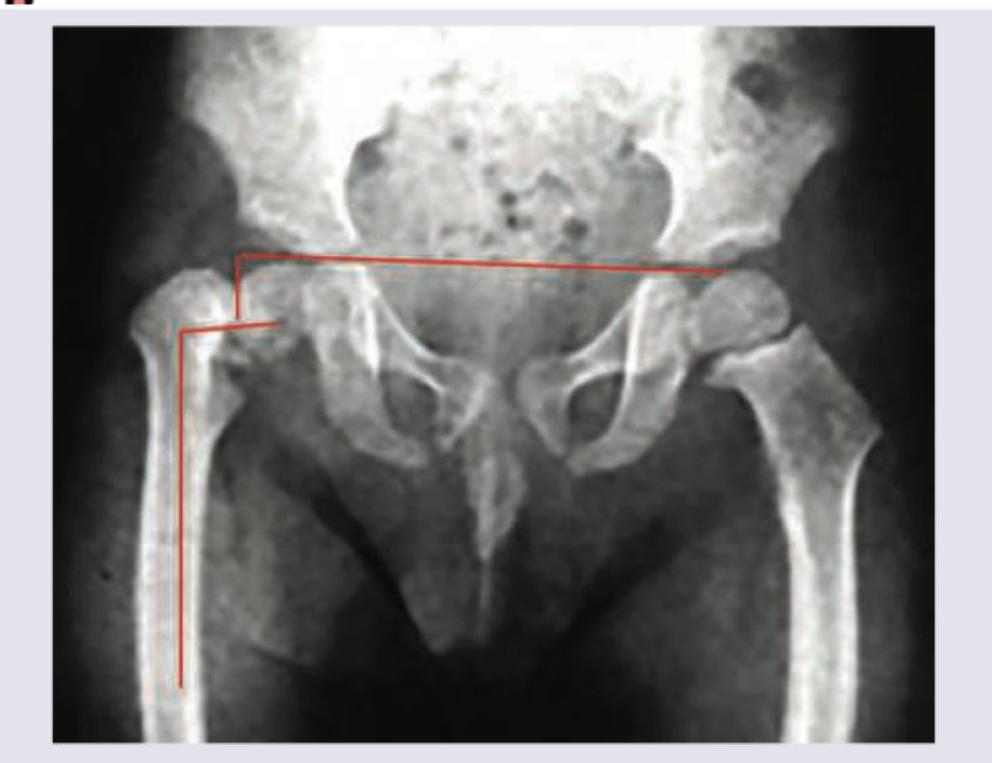

What does X-ray pelvis show?

Explanation: ***Coxa Vara*** - The image clearly shows a **decreased angle between the neck and shaft of the femur** on the left side, indicated by the red lines, which is characteristic of coxa vara. - Specifically, this typically means the **neck-shaft angle is less than 120 degrees**, causing the femoral head to be lower relative to the greater trochanter. *Coxa Valgum* - This condition is characterized by an **increased angle** between the neck and shaft of the femur (typically greater than 135 degrees), which is the opposite of what is seen here. - In coxa valga, the femoral head is positioned **higher** relative to the greater trochanter. *TB hip* - Tuberculosis of the hip would typically show signs of **joint destruction, osteopenia, or abscess formation**, none of which are evident in this image. - While TB can cause bone deformities over time, the primary finding here is a specific angular deformity, not infectious changes. *Developmental dysplasia of the hip* - Developmental dysplasia of the hip (DDH) involves **abnormal development of the hip joint**, leading to instability or dislocation of the femoral head from the acetabulum. - Common radiographic signs of DDH include an **underdeveloped acetabulum**, a high-riding femoral head, or increased acetabular index, which are not the primary findings demonstrated by the marked lines in this X-ray.